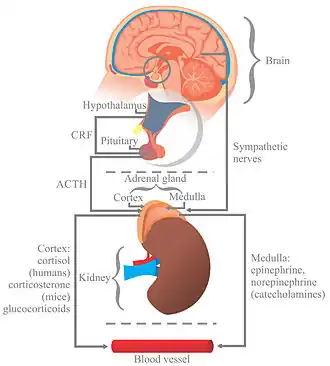

Stress, whether physiological, biological or psychological, is an organism's response to a stressor, such as an environmental condition or change in life circumstances.[1][2] When stressed by stimuli that alter an organism's environment, multiple systems respond across the body.[1] In humans and most mammals, the autonomic nervous system and hypothalamic-pituitary-adrenal (HPA) axis are the two major systems that respond to stress.[3][4] Two well-known hormones that humans produce during stressful situations are adrenaline and cortisol.[3][4]

The sympathoadrenal medullary axis (SAM) may activate the fight-or-flight response through the sympathetic nervous system, which dedicates energy to more relevant bodily systems to acute adaptation to stress, while the parasympathetic nervous system returns the body to homeostasis.[3][4]

The second major physiological stress-response center, the HPA axis, regulates the release of cortisol, which influences many bodily functions, such as metabolic, psychological and immunological functions.[4] The SAM and HPA axes are regulated by several brain regions, including the limbic system, prefrontal cortex, amygdala, hypothalamus, and stria terminalis.[3] Through these mechanisms, stress can alter memory functions, reward, immune function, metabolism, and susceptibility to diseases.[3][4]

The brain endocrine interactions are relevant in the translation of stress into physiological and psychological changes.[4] The autonomic nervous system (ANS) plays an important role by translating stress reflexively into a response both to physical stressors and higher level inputs by the brain.[31]

The ANS is composed of the parasympathetic nervous system and sympathetic nervous system, two branches that are both tonically active with opposing activities.[31] The ANS directly innervates tissue through the postganglionic nerves, which is controlled by preganglionic neurons.[31] The ANS receives inputs from the medulla, hypothalamus, limbic system, prefrontal cortex, midbrain and monoamine nuclei.[4][32]

The activity of the sympathetic nervous system drives what is called the "fight or flight" response.[4] The fight or flight response to emergency or stress involves increased heart rate and force contraction, vasoconstriction, bronchodilation, sweating, and secretion of the epinephrine and cortisol from the adrenal medulla, among numerous other physiological and hormonal responses.[31] The parasympathetic nervous response involves return to maintaining homeostasis, and involves miosis, bronchoconstriction, increased activity of the digestive system, and contraction of the bladder walls.[31] Complex relationships between protective and vulnerability factors on the effect of childhood home stress on psychological illness, cardiovascular illness and adaption have been observed.[4][33] ANS related mechanisms may increase the risk of cardiovascular disease after major stressful events.[4][34]

The HPA axis is a neuroendocrine system that mediates a stress response.[4] Neurons in the hypothalamus, particularly the paraventricular nucleus, release vasopressin and corticotropin releasing hormone, which travel through the hypophysial portal vessel where they travel to and bind to the corticotropin-releasing hormone receptor on the anterior pituitary gland.[4][31] Multiple CRH peptides have been identified, and their corresponding receptors exist in multiple brain regions, including the amygdala.[4] CRH is the main regulatory molecule of the release of ACTH.[4] The secretion of ACTH into the systemic circulation allows it to bind to and activate melanocortin receptors, where it stimulates the release of steroid hormones.[4] The immune system may be influenced by stress. The HPA axis ultimately results in the release of cortisol, which generally has immunosuppressive effects.[4]